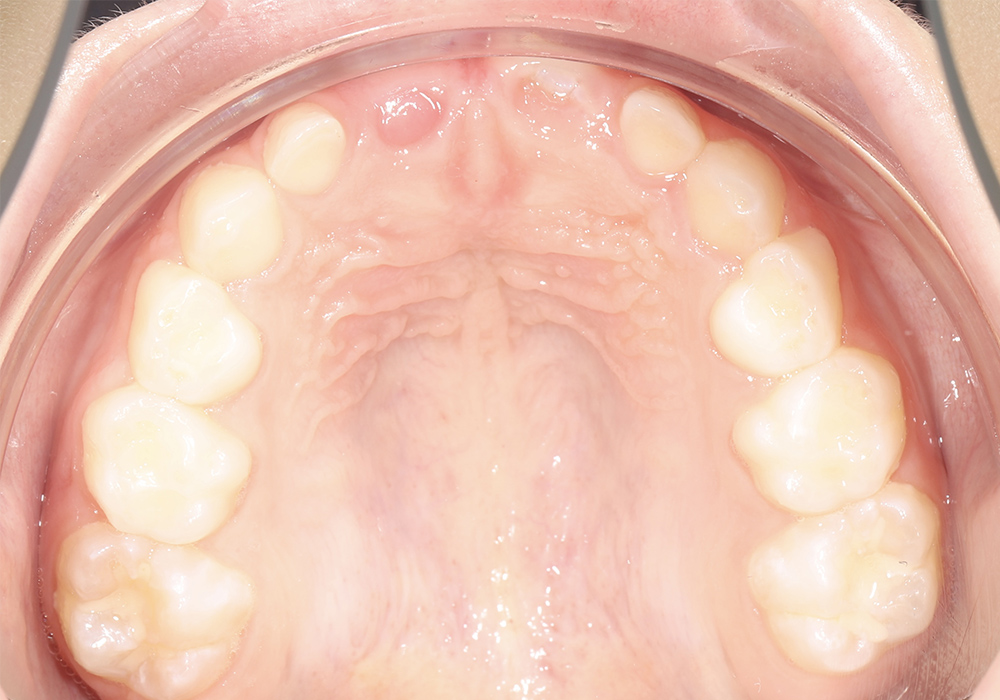

Комплексное ортодонтическое лечение ребенка 8 лет со сверхкомплектным центральным резцом